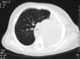

Mediastinal shift is the deviation of the mediastinal structures towards one side of the chest cavity, usually seen on chest radiograph. It indicates a severe asymmetry of intrathoracic pressures. [Source: Wikipedia ]